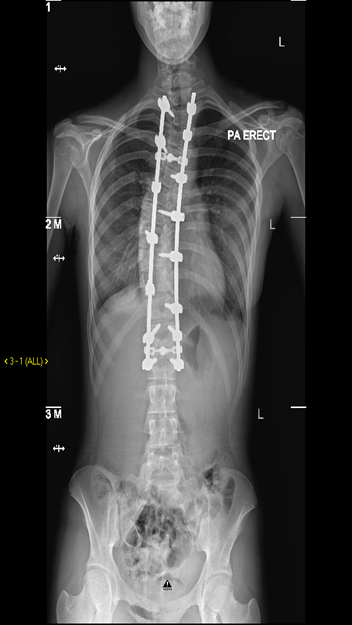

It can range from close monitoring in our dedicated scoliosis clinics with regular x ray follow-up to surgical correction of the curve.